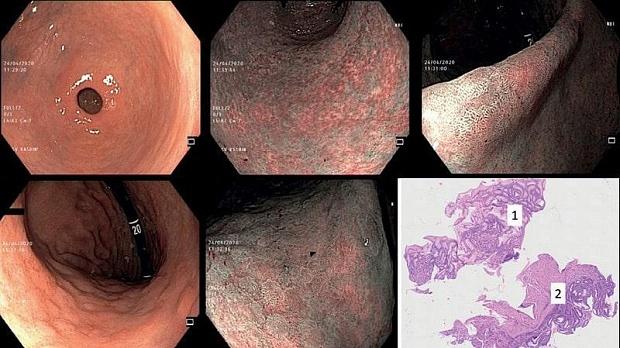

Положение 6. Эндоскопия высокого разрешения с хромоскопией является более точным методом диагностики предраковых состояний/изменений слизистой оболочки желудка по сравнению с эндоскопией в белом световом режиме (рис. 5—9).

Рис. 6. а, б, в, г, д — эндоскопическое исследование с применением системы Olympus EVIS EXERA III и узкоспектральным режимом осмотра NBI: атрофический гастрит антрального отдела и области угла желудка с очагами кишечной метаплазии, диагностика очагов кишечной метаплазии в теле желудка; е — гистологическое исследование: хронический атрофический мультифокальный гастрит с фокусами кишечной метаплазии, фокус фовеолярной гиперплазии (1) и фокус кишечной метаплазии (2) в пределах одного биоптата.